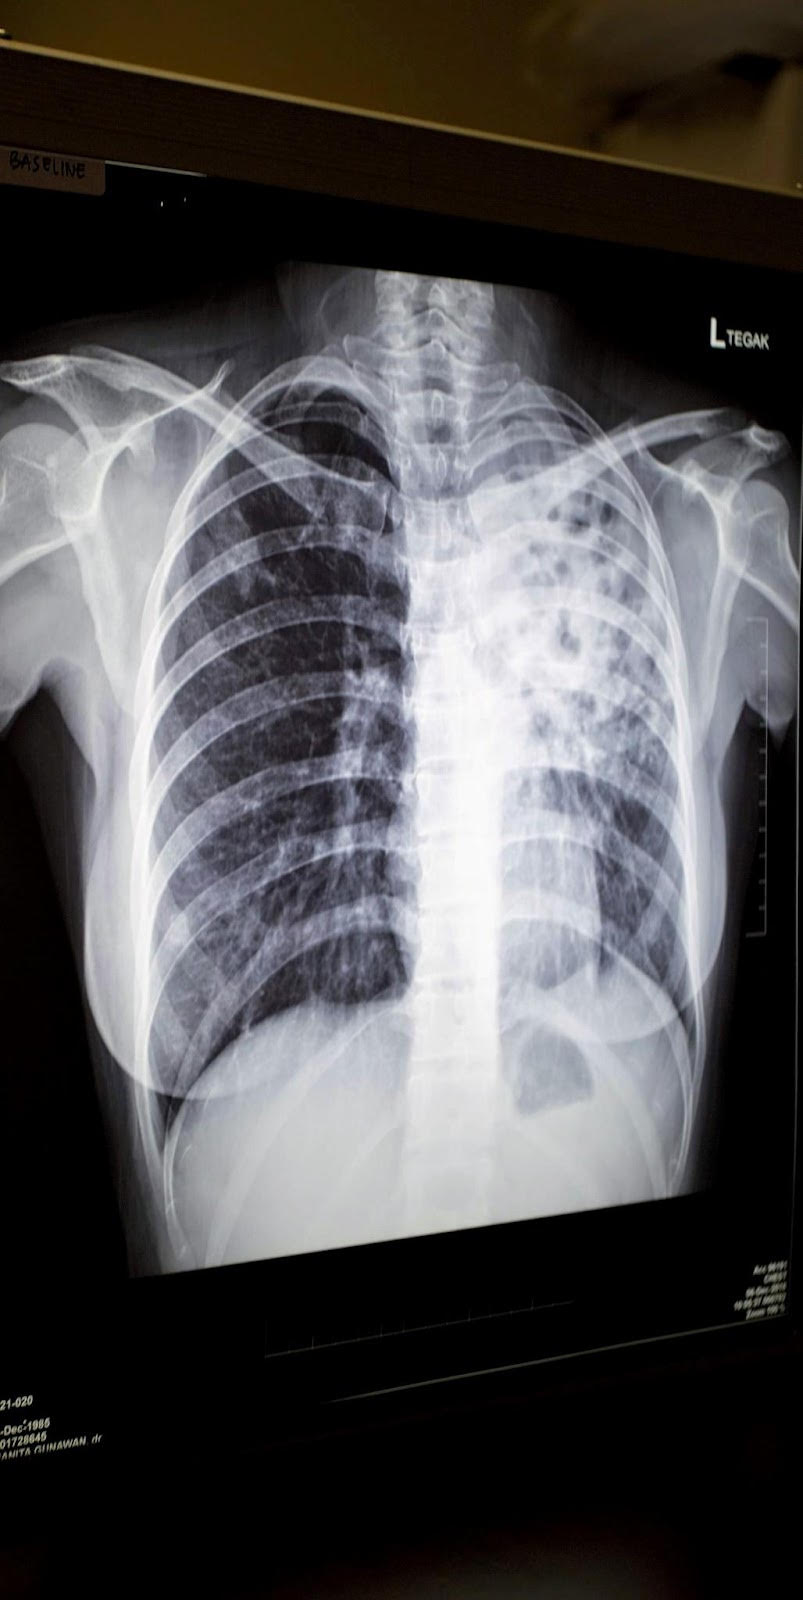

- Foto toraks pasien yang terdiagnosa TB paru (Photo credit: Pearl Gan untuk OUCRU Indonesia)